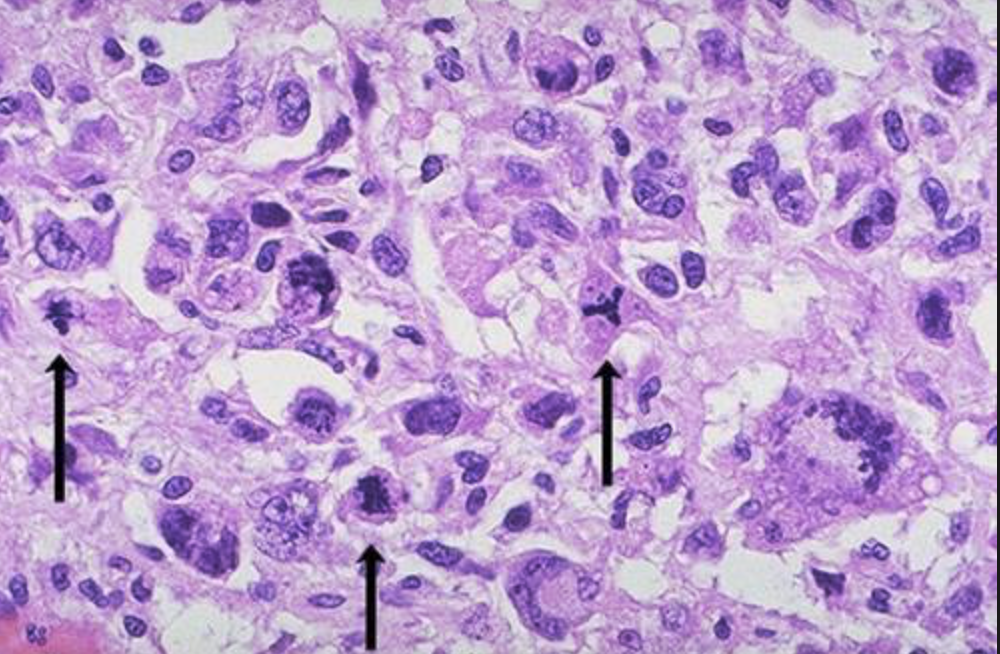

Akut leukemi

Malign tumör utgående från omogna celler (blastceller) i de olika poeserna i benmärgen, och spridning till blod, med blastceller i blod (>20%) och/eller benmärg (>20%).

Bilden: Akut lymfatisk leukemi.